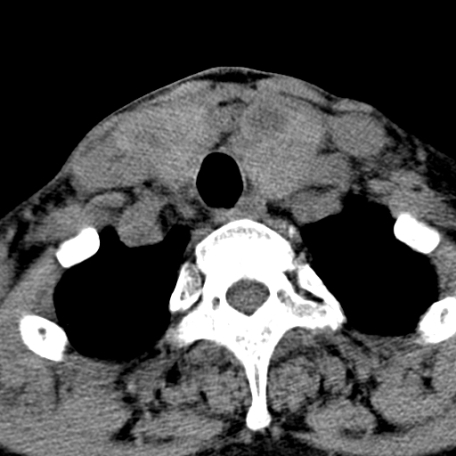

标题: CT24010:患者女56岁双侧甲状腺摘除术后一月复查,患者现感 [打印本页]

标题: CT24010:患者女56岁双侧甲状腺摘除术后一月复查,患者现感

甲状腺术后复发,现在甲状腺区域仍有密度不均匀之软组织密度影。

甲状腺区域密度不均匀密度影,应该是术后改变,要鉴别是否复发,建议增强检查。

“甲状腺摘除术后一月复查”,有病理吗?考虑术后复发,可能是恶性,颌下及左侧颈部淋巴结有肿大。

考虑术后复发,并颈部淋巴结肿大。请结合临床。

双侧甲状腺肿大,周围结构不清,术后复发时间有点短,考虑出血并感染。